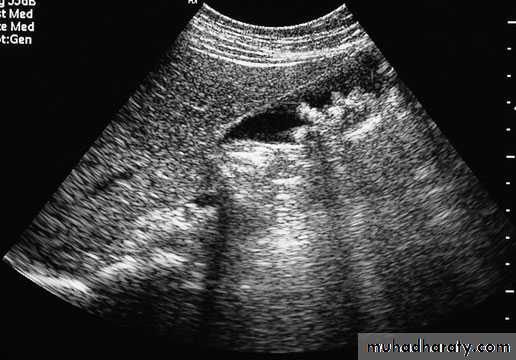

This is the first-line test owing to its safety and availability.

It is entirely operator dependent.It is useful for determining bile duct dilatation, the presence of gallstones and the presence of liver tumours.

Doppler ultrasound allows flow in the hepatic

artery, portal vein and hepatic veins to be assessed.

In some countries, it is used as a screening test for the development of primary liver cancers in a high-risk population.

Ultrasound is useful in guiding the percutaneous biopsy of a liver lesion

Ultrasound